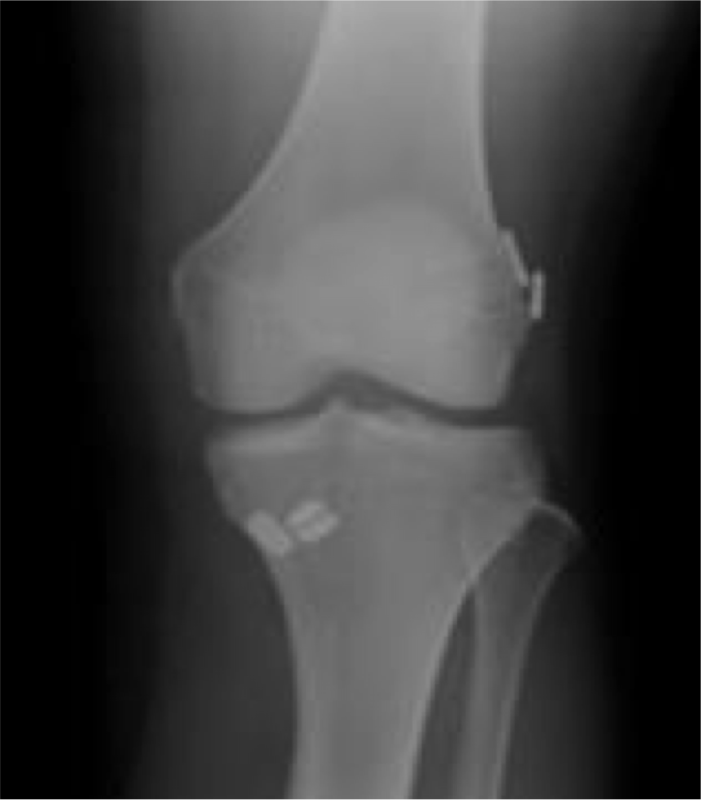

レントゲン

術前術後

骨傷や変OA変化等なし異常所見なし